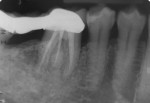

The intraoral periapical radiograph of the mandibular right first molar (tooth No. 30) showed radiolucency around the periapex with severe bone loss (Figure 3). Careful observation of this radiograph showed the presence of an additional distolingual root in relation to this tooth. The radiograph showed radiolucency in the furcation area with inter-radicular bone loss extending up to the apex of the distal and distolingual roots. Endodontically, the diagnosis was chronic apical abscess associated with necrotic pulp. Due to the associated advanced periodontal destruction, this lesion was classified as an endodontic-periodontal lesion. The formulated treatment plan comprised of drainage of the periodontal abscess with adjunctive antibiotics, phase I periodontal therapy (scaling and root surface debridement), endodontic therapy, and radiculoplasty, followed by regenerative periodontal therapy and replacement of the missing right mandibular second molar.

Follow-up of the patient at 3 months, 6 months (Figure 9 and Figure 10), and 9 months (Figure 11 and Figure 12) was uneventful. Grade I mobility had been detected at 1 month. Oral prophylaxis done at three monthly intervals and a prescription of interdental cleaning aids has helped the patient maintain oral hygiene. At the 9-month follow-up, probing depth at tooth No. 30 was 3 mm buccally and 4 mm lingually. Radiographs at 9 months (Figure 13) showed radioopacity around the distolingual root, an evidence of continued hard-tissue healing.